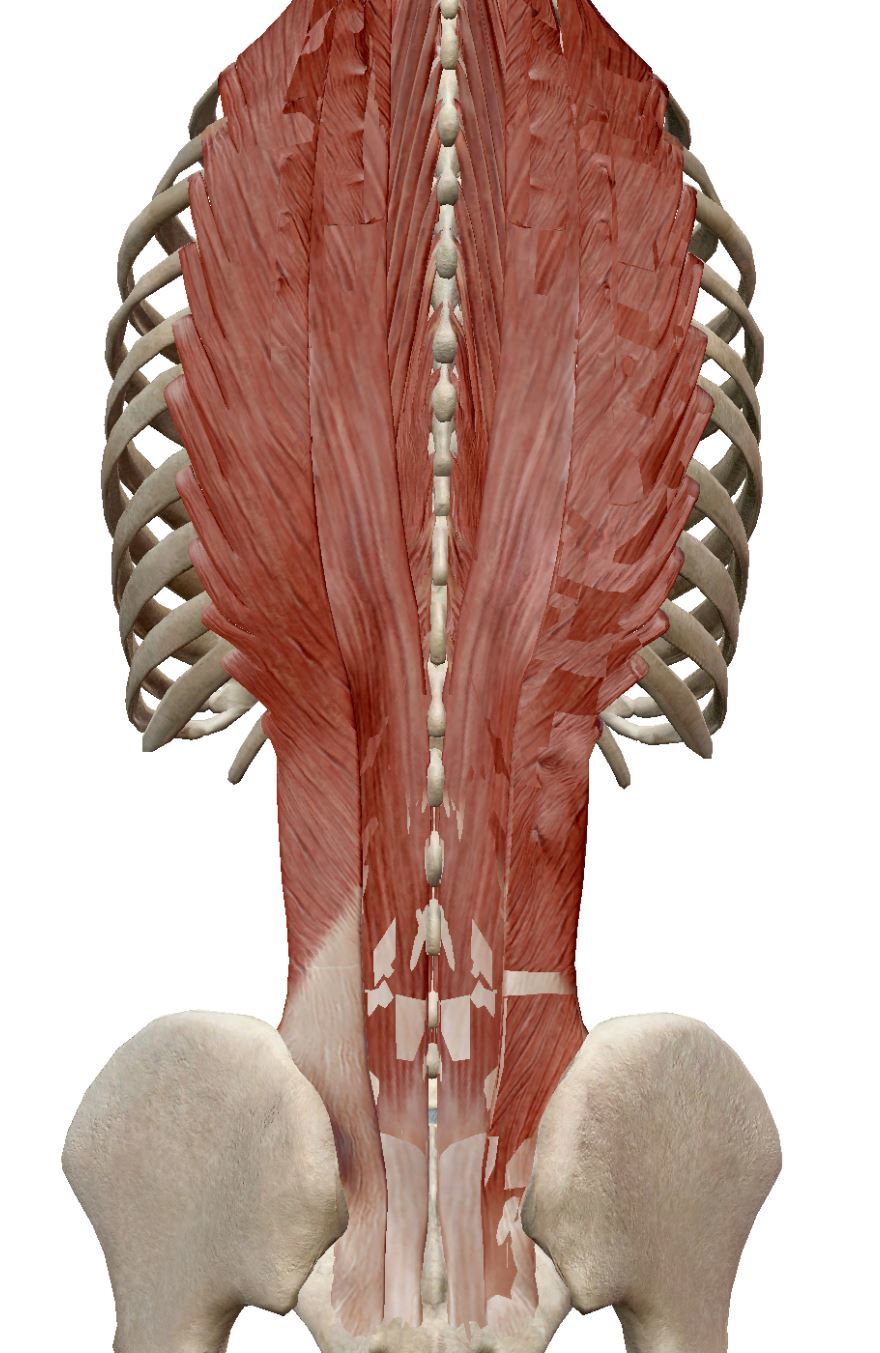

脊柱生理曲度是由腰背部的肌肉、以及腹部的肌肉所共同影响的。正常情况下是处于动态平衡的【1】。脊柱的屈伸活动,主要是由腰背部肌肉(见下图)所控制。

当我们感到腰痛的时候,腰背部脊柱椎旁肌肉肌肉会出现痉挛。这被认为是一种保护性机制,痉挛的腰背部肌肉像一个夹板一样,保护受伤的脊柱【2】。腰背部肌肉的痉挛时,失去维持脊柱生理曲度的功能,会导致腰椎生理曲度变直。

文献证实,强大的腰背部肌肉可以让腰椎曲度变得更为正常【1】。因此在腰痛消失后,应该积极进行腰背部肌肉锻炼,推荐“小燕飞”锻炼、游泳等。小燕飞锻炼详细教程(请点击)